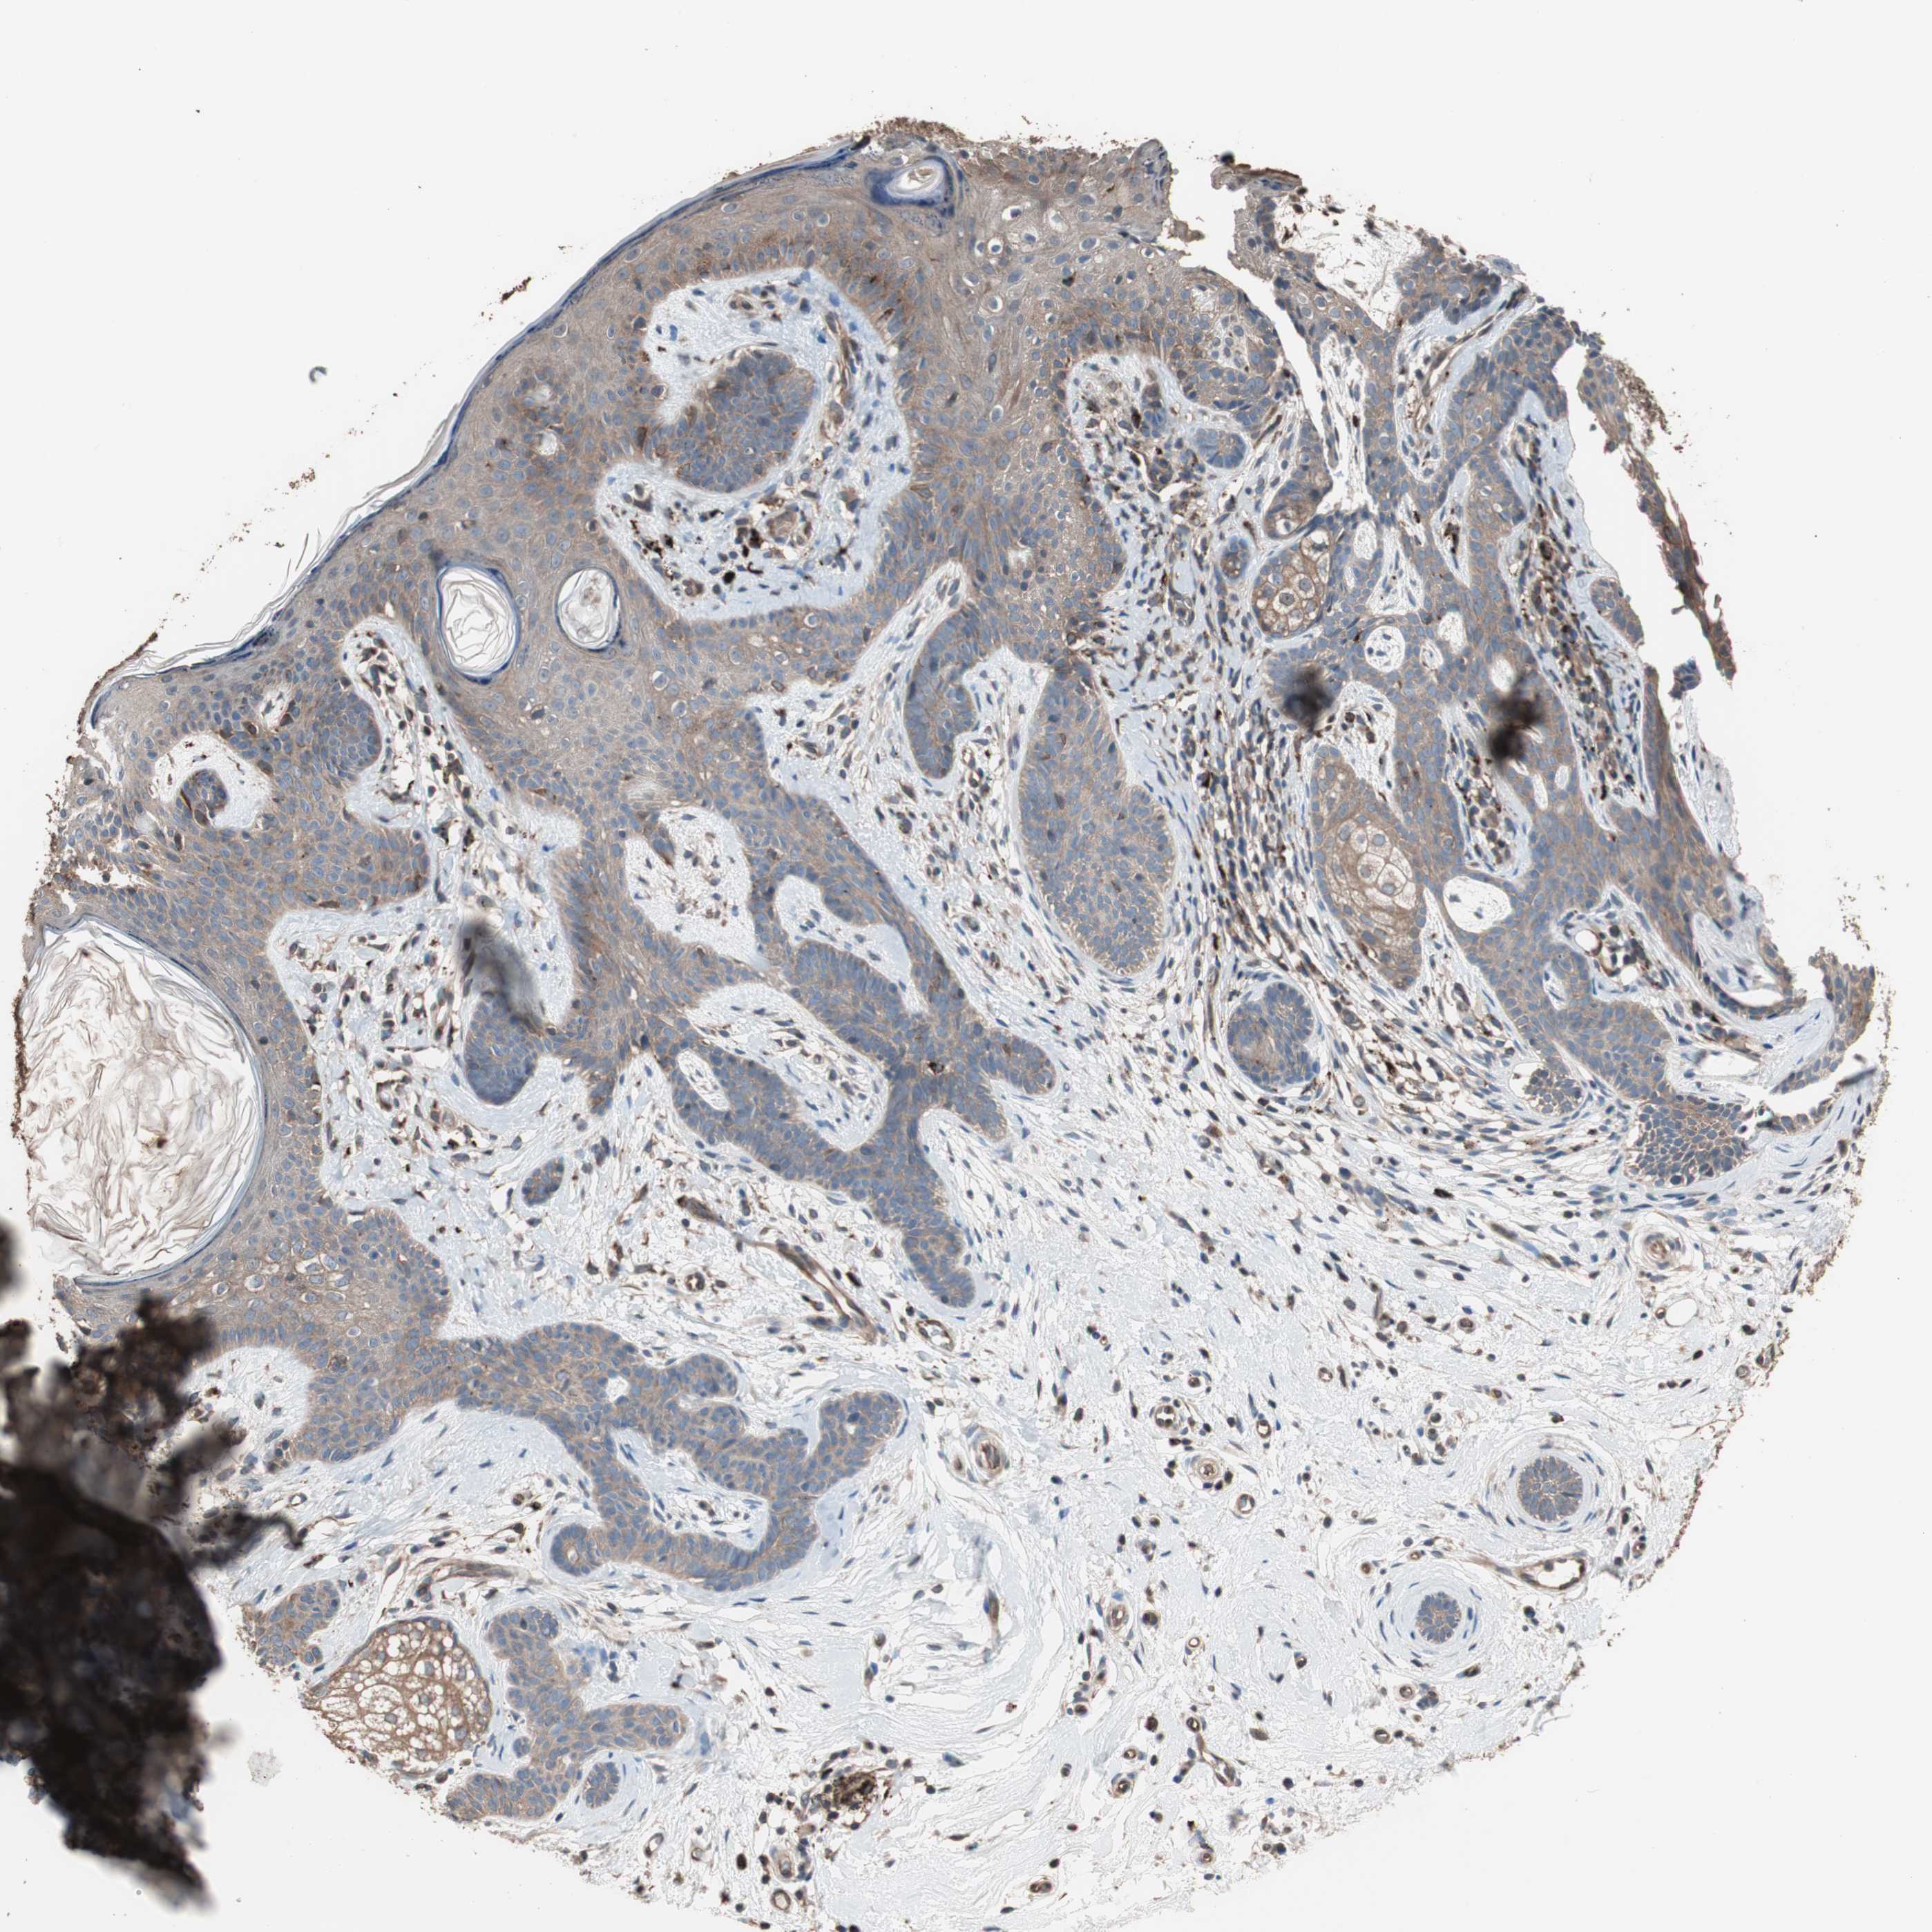

SKIN CANCER - Protein expressioni

A mouse-over function shows sample information and annotation data. Click on an image to view it in a full screen mode. Samples can be filtered based on level of antibody staining by selecting one or several of the following categories: high, medium, low and not detected. The assay and annotation is described here.

Antibody stainingi

Antibody staining in the annotated cell types in the current human tissue is reported as not detected, low, medium, or high, based on conventional immunohistochemistry profiling in selected tissues. This score is based on the combination of the staining intensity and fraction of stained cells.

Each image is clickable and will lead to virtual microscopy that enables deeper exploration of all samples and also displays staining intensity scores, fraction scores and subcellular localization as well as patient and tissue information for each sample.

Antibody HPA006543

Staining

Medium

Intensity

Moderate

Quantity

75%-25%

Location

Cytoplasmic/membranous,nuclear

Basal cell carcinoma